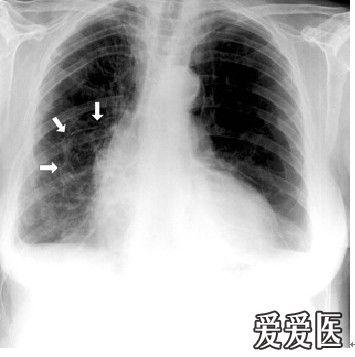

气胸影像图片,气胸胸片典型图片

呼吸版经验交流(7)气胸:影像学解读指南

关于气胸的x光片